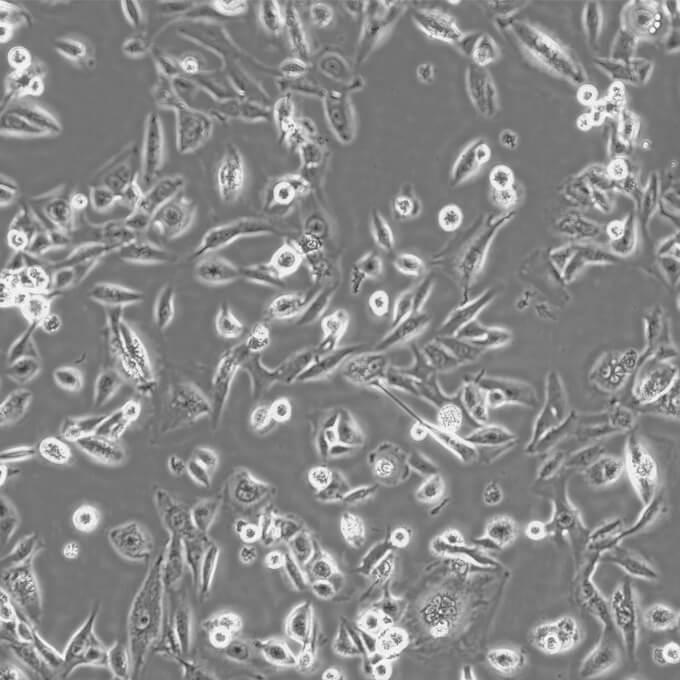

MDA-MB-435S细胞(人乳腺导管癌细胞)

形态 上皮细胞样

生长特性 贴壁

背景描述 MDA-MB-435S是一种纺锤形的细胞,1976年由其亲本(MDA-MB-435)中筛选得到。MDA-MB-435是从一名31岁的转移性乳腺导管腺癌女性患者胸水中分离得到的。但近来证明MDA-MB-435细胞被M14黑色素瘤细胞污染。